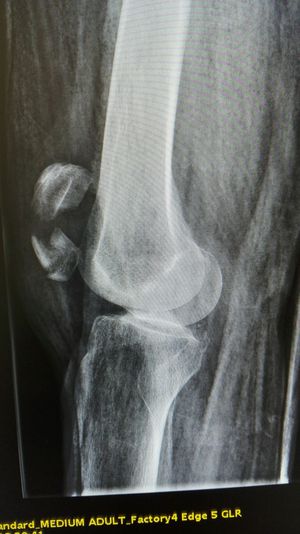

Xray

Fracture

Patella